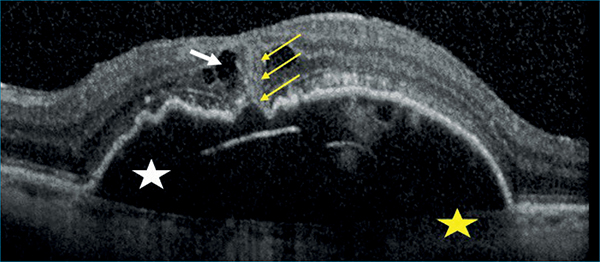

3-as típusú MNV/RAP esetén Kim és munkatársai úttörő vizsgálatot végeztek, amelyben 236 szem elemzése során RAP-léziót PCV-től és típusos nAMD-től 88%-os szenzitivitással és 95%-os specificitással sikerült elkülöníteni ICGA-alapú diagnózissal szemben, amennyiben a következő 5 OCT-kritériumból legalább 3 teljesült:

- subfovealis chorioidealis vastagság <200 µm;

- intraretinalis folyadék (IRF) jelenléte;

- subretinalis folyadék (SRF) hiánya;

- enyhén lejtős domb alakú (a lejtő <45° meredekségű 1:1 pixel méretarányú képen mérve) vagy trapéz alakú PED egyértelmű csúcs nélkül;

- intraretinalis hiperreflektív massza jelenléte (8. ábra) (22).

• subfovealis chorioidealis vastagság <200 µm (sárga csillag),

• intraretinalis folyadék (IRF) jelenléte (fehér nyíl),

• subretinalis folyadék (SRF) hiánya,

• enyhén lejtős domb- vagy trapézalakú pigmentepithel-leválás (PED) egyértelmű csúcs nélkül (fehér csillag),

• intraretinalis hiperreflektív massza jelenléte (sárga nyilak)